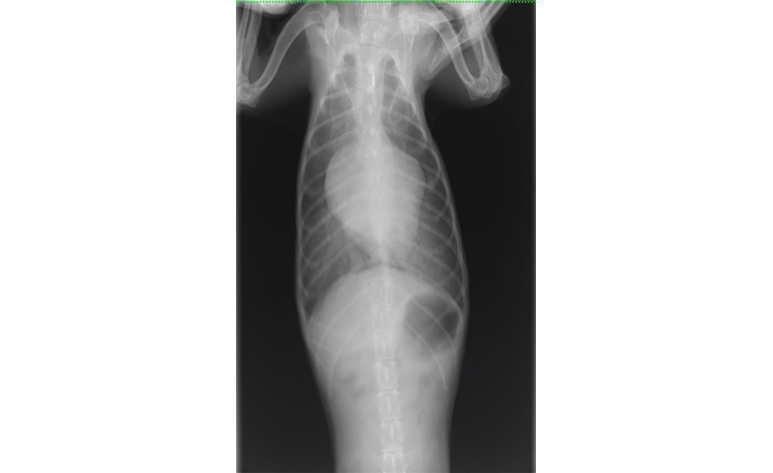

| 検査 | 身体検査、聴診、レントゲン検査、超音波検査、心電図検査、血圧測定、血液検査 |

症状や検査結果を基に、薬の種類や量を決めていきます。また、病状の進行によって種類、量が変わるので、定期的な検査をします。

心臓病の検査で特に大きな要となるのが、超音波検査でありますが、大変高い技術が求められる検査であります。この技術により診断が左右することも大いにあります。当院では幅広い知識と高い技術で検査を行い、診断しております。この検査では、動物に横になったり、仰向けになったりしてもらいますが、その姿勢が苦手な子、またその姿勢によって息苦しくなってしまう子に対しては、立ったままの姿勢での検査を行っております。